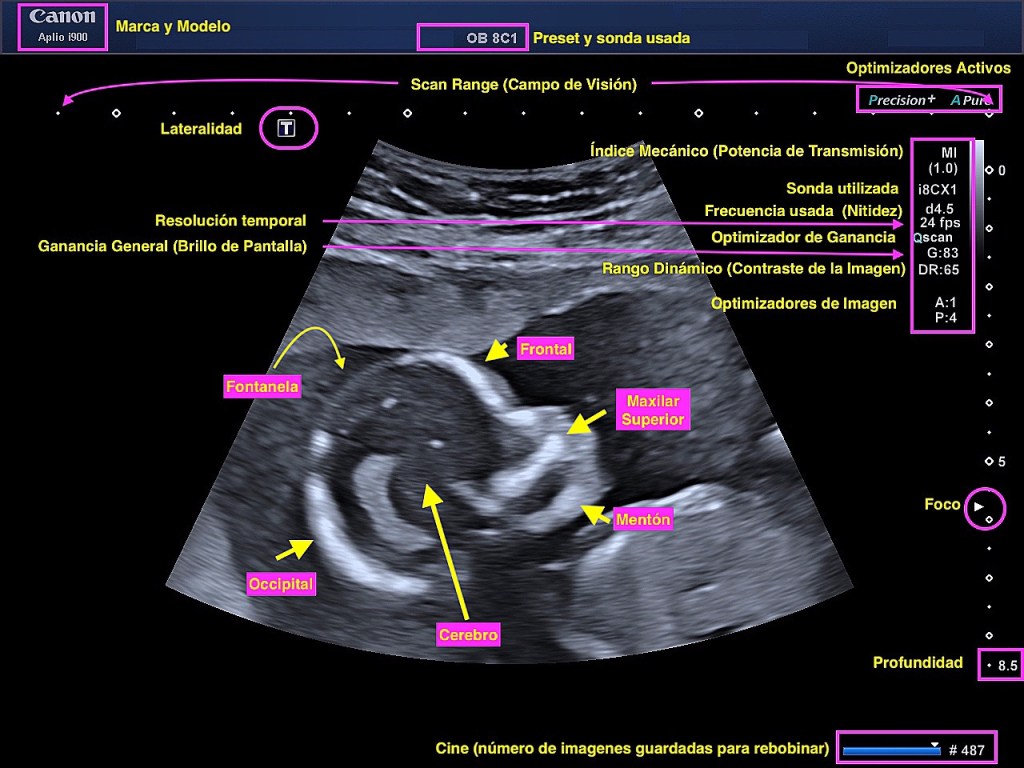

Lo que nos cuenta un imagen de ecografía y no nos fijamos.

🟣Datos demográficos

🟣Marca y modelo del Equipo

🟣Sonda y Preset usada

🟣Aspecto técnicos y de calidad de la imagen (esos que casi nadie mira 😉)

🟣Y luego…la anatomía ecográfica estudiada💞

Imagen espectacular de un #Aplioi900 de Canon Medical Systems Europe trabajo conjunto con @marialealgondra